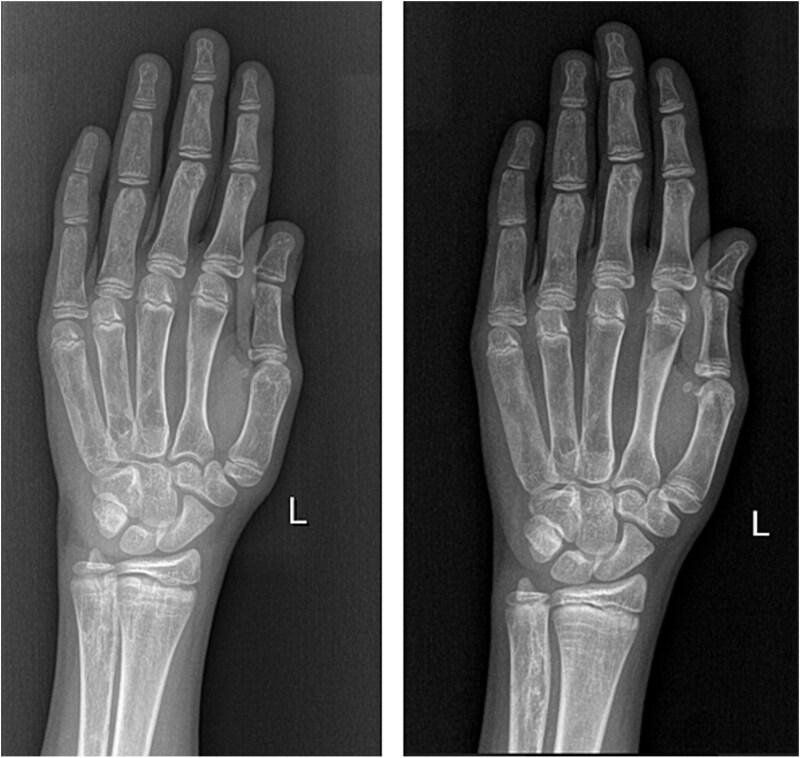

Fibrous dysplasia/McCune-Albright syndrome (FD/MAS) is a rare condition caused by a mutation in the GNAS locus. Apart from endocrinopathies, some cases are characterized by excessive fibroblast growth factor 23 (FGF23) production from abnormal fibro-osseous tissue in FD lesions, resulting in increased renal phosphate excretion. We present a girl with FD/MAS and severe skeletal burden, evidenced by the presence of polyostotic fibrous dysplasia, which was complicated with bone fractures. She also had hyperthyroidism and GnRH-independent precocious puberty. She received zoledronic acid infusions in preparation for hip surgery. Despite optimal conventional management with oral phosphate and alphacalcidol, which was poorly tolerated, she presented persistent hypophosphatemia. To control hypophosphatemia and its deleterious effects on bone health, treatment with burosumab off-label at a dose of 0.66 mg/kg (20 mg) every 2 wk was initiated. Serum phosphate levels normalized within 2 wk of treatment. Laboratory results showed improvement in serum alkaline phosphatase (ALP) and PTH levels. After the second injection of burosumab, phosphate and PTH rose above the normal range with normal vitamin D levels; therefore, the interval between doses was increased to 3 wk, and calcium 500 mg daily was added. However, phosphate levels dropped again below normal range, so she had to return to 2-weekly injections of 20 mg. After 11 mo on burosumab, she remains with high normal phosphate levels and normal PTH and ALP values. Burosumab is well tolerated, with no adverse events to date. Burosumab is a human monoclonal antibody against FGF23 that reduces the risk of developing FGF23-mediated hypophosphatemia and its associated complications. Burosumab should be considered as an effective and safe alternative strategy for FGF23-mediated hypophosphatemia in FD/MAS for those who either cannot tolerate or do not respond to conventional therapy. To our knowledge, this is the fourth published case worldwide describing successful treatment with burosumab in FD/MAS.

纤维性骨发育不良/麦库恩-奥尔布赖特综合征(FD/MAS)是一种由GNAS基因座突变引起的罕见疾病。除内分泌病外,一些病例的特征是FD病变中异常纤维-骨组织过度产生成纤维细胞生长因子23(FGF23),导致肾脏磷酸盐排泄增加。我们报告一名患有FD/MAS且骨骼负担严重的女孩,多骨型纤维性骨发育不良证明了这一点,该病并发了骨折。她还患有甲状腺功能亢进和GnRH非依赖性性早熟。她接受了唑来膦酸输注以准备髋关节手术。尽管采用口服磷酸盐和阿法骨化醇进行了最佳的常规治疗,但耐受性较差,她仍持续存在低磷血症。为了控制低磷血症及其对骨骼健康的有害影响,开始使用布罗索尤单抗进行超说明书用药治疗,剂量为每2周0.66mg/kg(20mg)。治疗2周内血清磷酸盐水平恢复正常。实验室结果显示血清碱性磷酸酶(ALP)和甲状旁腺激素(PTH)水平有所改善。第二次注射布罗索尤单抗后,磷酸盐和PTH升至正常范围以上,维生素D水平正常;因此,剂量间隔增加到3周,并每天添加500mg钙。然而,磷酸盐水平再次降至正常范围以下,因此她不得不恢复每2周注射20mg。使用布罗索尤单抗治疗11个月后,她的磷酸盐水平仍保持在高正常范围,PTH和ALP值正常。布罗索尤单抗耐受性良好,迄今为止未发生不良事件。布罗索尤单抗是一种抗FGF23的人单克隆抗体,可降低发生FGF23介导的低磷血症及其相关并发症的风险。对于那些无法耐受或对传统治疗无反应的FD/MAS患者,布罗索尤单抗应被视为治疗FGF23介导的低磷血症的一种有效且安全的替代策略。据我们所知,这是全球第四例发表的使用布罗索尤单抗成功治疗FD/MAS的病例。